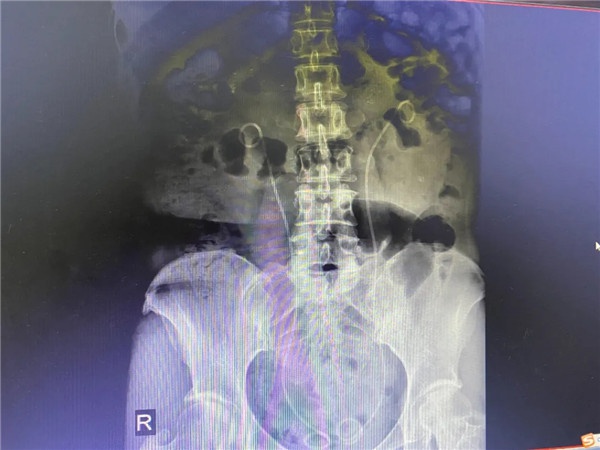

經(jīng)過B超和CT檢查,發(fā)現(xiàn)患者的雙腎、雙側(cè)輸尿管都有結(jié)石,造成雙腎重度積水,嚴重影響了腎功能。在外三科付衛(wèi)國主任看來,像小英這樣的慢性腎結(jié)石患者,“危險系數(shù)”比急性患者更大,雙腎結(jié)石、輸尿管結(jié)石并有腎積水,且結(jié)石較大,形成雙側(cè)輸尿管梗阻,排尿困難。檢驗科檢測,患者尿酸和肌酐、血鉀都已經(jīng)達危急值,情況比較嚴重,建議盡快手術(shù),否則過不了多久可能會導(dǎo)致無尿、急性腎功能衰竭或者發(fā)展下去就可能是腎臟功能喪失,引發(fā)尿毒癥?!?/p>

術(shù)前,結(jié)石清晰可見;術(shù)后,結(jié)石被成功取出。